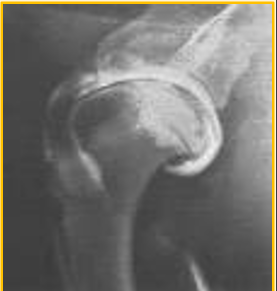

Arthrography - used for ..

Elevate peripheral joints, in particular, the shoulder

Osteochondrosis

Arthrography - preferred contrast

Positive contrast arthrogram preferred

Arthrography - Contrast studies

Negative and double contrast studies may cause air bubbles to mix with the synovial fluid in the joint space interpretation difficult

Arthrography

Not a routine procedure → Performed most commonly in orthopaedic referrals. CT and MRI often used instead of this imaging technique